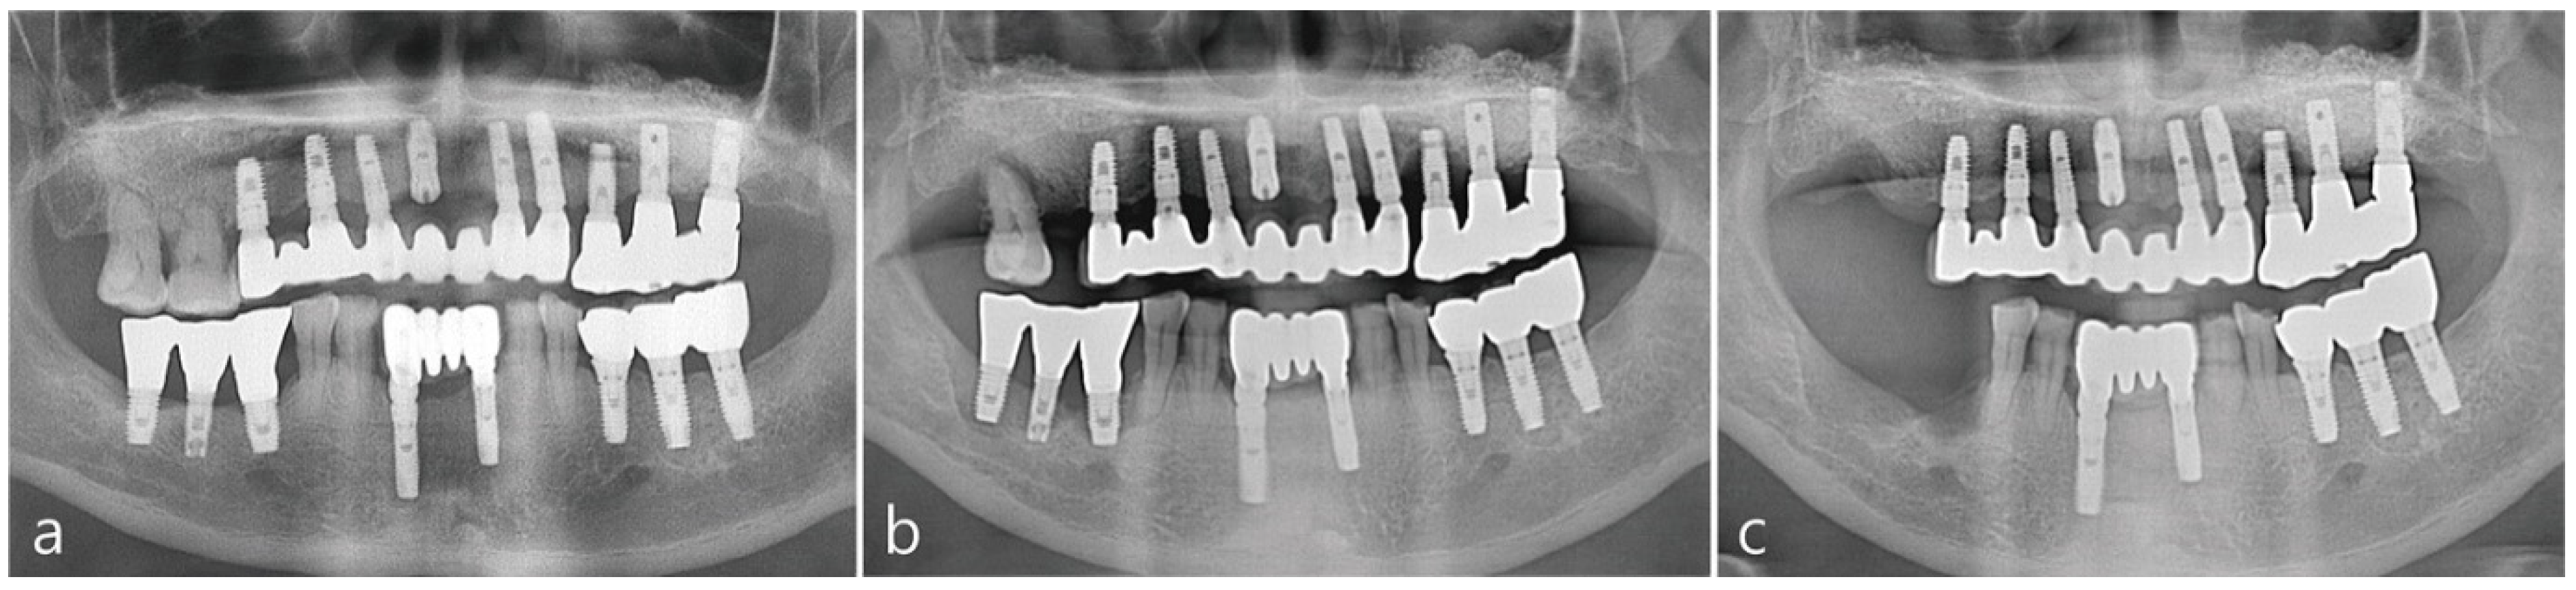

Prophlyaxis 2 g of amoxicillin was administered 1 h before surgery. Under local anesthesia with 2% lidocaine containing 1:100,000 epinephrine, the buccal and palatal mucoperiosteal flap was reflected for implant placement as shown in Figure 2a. Vertical bony defects were present in the partially healed extraction socket. Autogenous bone was harvested twice using an Ø 4.0 mm trephine drill (Zimmer Biomet, Warsaw, IN, USA) from the lateral surface of the maxilla apical to the implants as illustrated in Figure 2b. One of the two bone cores was fixed in neutral buffered formalin solution (Sigma-Aldrich, St. Louis, USA) for biopsy and the other was crushed into a size of 1–3 mm to be used as bone graft shown in Figure 2b,c respectively. A SLA-textured implant (Ø 4.3 × 12 mm Implantium, Suwon, Korea) was placed in the extraction socket. Due to the ridge deficiencies, the implant platform was placed supracrestally to accomadate for ideal implant placement as depicted in Figure 2e. The crushed harvested bone was placed into the mesial bony defect around the implant and supracrestally around the implant up to the implant platform as seen in Figure 2f. The site was covered with an resorbable collagen membrane (Genoss, Suwon, Korea) as shown in Figure 2g respectively. The flaps were sutured tension-free using 4-0 nylon, but as shown in Figure 2h, the membrane was partially exposed at the extraction socket site; primary closure was not achieved.

Figure 2. (a) Intra-oral photo of upper right maxillary quadrant 2 months post extraction (b) Utiliziation of a trephine bur to collect bone from previously augmented right maxillary sinus. (c) Bone was harvested twice for histologic analysis and utilization for new implant site (d) Intra-oral photo of the size of bone core obtained. (e) New implant was placed in previous extraction site and the implant platform was supracrestal to the ridge to allow for vertical bone augmentation. Vertical intra-osseous defect was present on the mesial surface of the implant. (f) Harvested bone core was crushed and placed into the intra-osseous defect. (g) The surgical site was covered with an resorbable collagen membrane. (h) The flap was closed tension-free. The membrane was partially exposed at the extraction site.